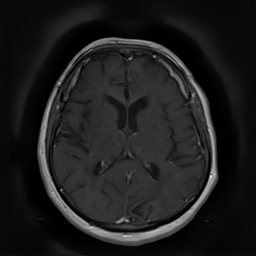

(a) Guide 𝑮𝑮\boldsymbol{G}

Refer to caption

(b) Input 𝑰𝑰\boldsymbol{I}

(c) Guidance map 𝑴𝑴\boldsymbol{M}

(d) Prediction 𝑷𝑷\boldsymbol{P}

(e) Ground truth

Figure 2: Inputs and outputs of the guided filtering pipeline based on the WDSR network. T1 & T2 MRI pairs (a)-(e) and CT & MRI projection images (f)-(j).